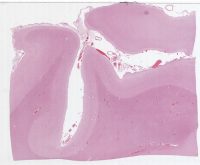

AANP2002-11.svs

8000 x 8187

@ 20X